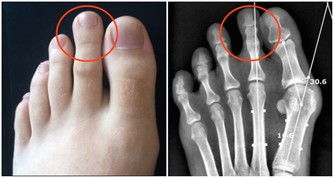

*****三、腳趾增大、增粗*****

正常的人體腳趾在成年後基本上不會發生太大的變化,包括外形、大小等等。但是突然發現多個腳趾有增大、增粗的症狀,腳指甲厚度增加,這就是臨床上所謂的“杵狀指”,杵狀指的出現往往意味著可能患上了肺部慢性疾病。